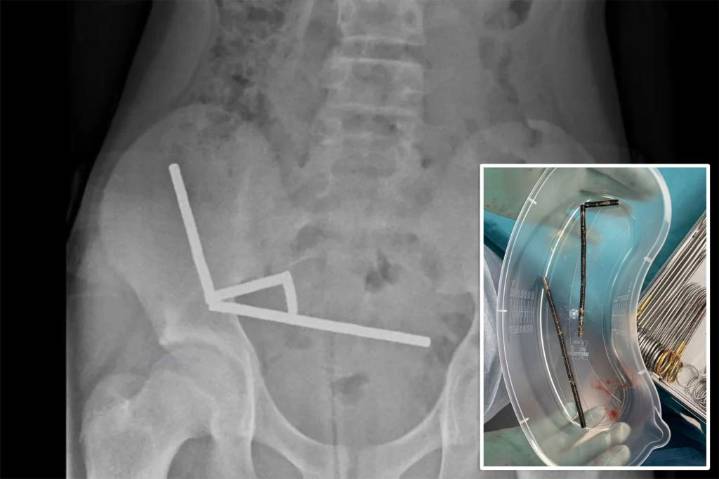

X-rays revealed four chains of magnets lodged in different sections of his intestines, pulling together and cutting off blood flow to nearby tissue. 3

Doctors said the pressure caused multiple patches of necrosis — areas of dead inte